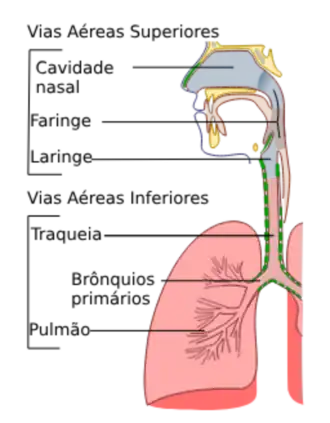

Aparelho respiratório e Passagem de ar

Vias aéreas superiores

Vias aéreas inferiores

Em mamíferos típicos, como humanos, abaixo das "vias aéreas superiores" (as fossas nasais, a faringe e a laringe), encontra-se a árvore respiratória ou árvore traqueobrônquica (figura à direita).

As vias aéreas maiores dão origem a ramos que são ligeiramente mais estreitos, mas mais numerosos do que a via aérea "tronco" que dá origem aos ramos. A árvore respiratória humana pode consistir, em média, em 23 dessas ramificações em vias aéreas progressivamente menores. As divisões proximais (aquelas mais próximas do topo da árvore, como a traqueia e os brônquios) funcionam principalmente para transmitir ar para as vias aéreas inferiores. Divisões posteriores, como os bronquíolos respiratórios, ductos alveolares e alvéolos, são especializados para a troca gasosa.

A traqueia e as primeiras porções dos principais brônquios estão fora dos pulmões. O restante da "árvore" se ramifica dentro dos pulmões e se estende a todas as partes deles.